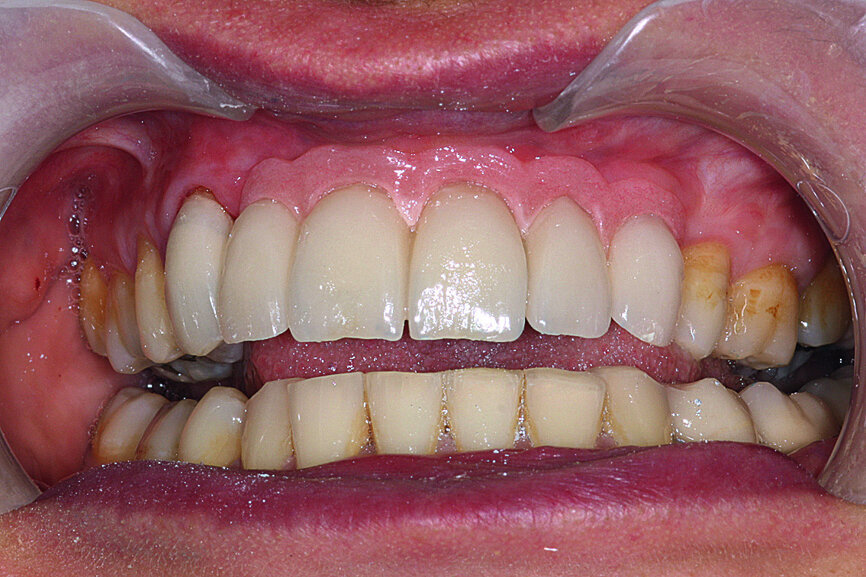

Fig. 28: The prosthesis was attached with screws and the necessary occlusal verification was conducted.

Fig. 29: The prosthesis was attached with screws and the necessary occlusal verification was conducted.

Fig. 30: The patient’s smile showing now well-balanced

incisors in line with the face’s sagittal plane, lip support appearing to be correct.

In the following step, the prosthesis was attached in the mouth with screws and the necessary occlusal verification was conducted, including maximum intercuspation, protrusion and lateral excursion. The natural canine on the right was also equipped with a verification tooth. It should be noted, that in lateral excursion on the left, with the antagonist being the original tooth equipped with its periodontal ligament receptors, the canine function was retained; however the group function, which is usually preferred, was neurophysiologically inept (Figs. 28 & 29).

The patient’s smile showed that the incisors were now well balanced and in line with the face’s sagittal plane. Lip support appeared to be correct and, as often is the case, this would all be validated by the patient’s surrounding friends and family (Fig. 30).